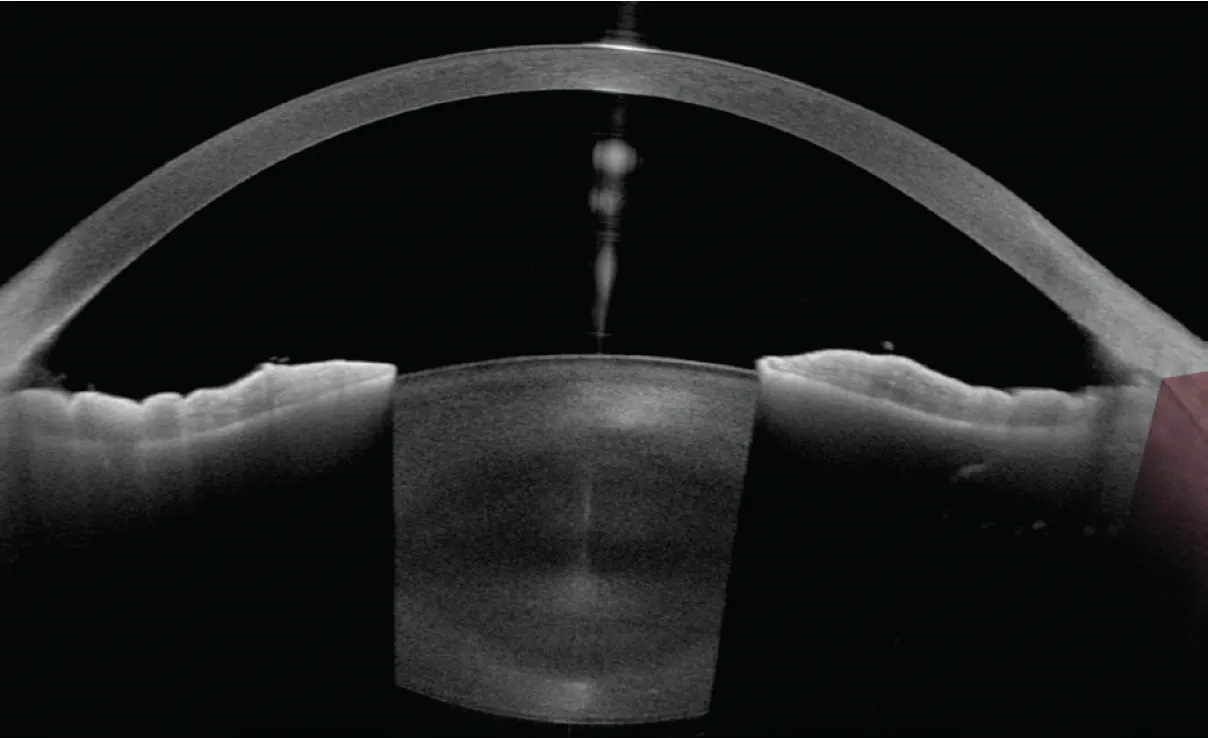

Central corneal thickness measures 581 µm OD and 580 µm OS. Corneal hysteresis is within the average range (9.5 OD and 9.4 OS). A slit-lamp examination finds classic signs of pigment dispersion, including iris transillumination defects, dense (4+) trabecular meshwork pigmentation, and pigment deposition on the corneal endothelium. Anterior segment OCT confirms posterior iris bowing (Figure 1).

Figure 1. Anterior segment OCT of the right eye demonstrating posterior iris bow. Both eyes share similar anatomy.